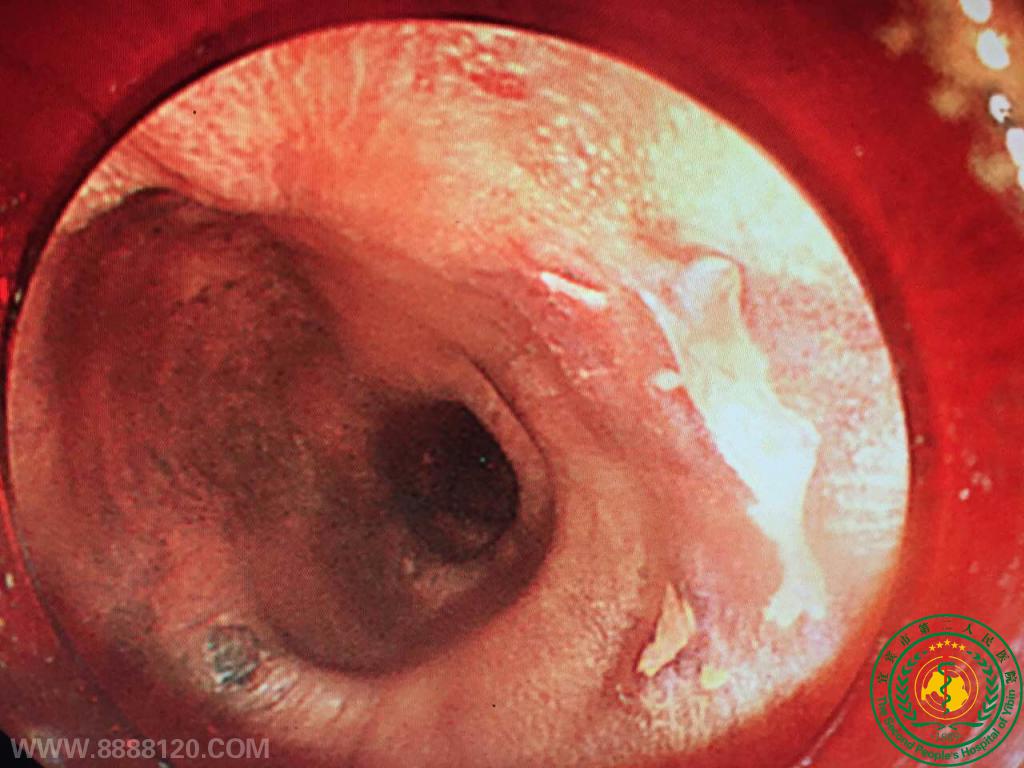

消化科成功实施宜宾市第一例早期食管癌胃镜下切除

消化科成功实施宜宾市第一例早期食管癌胃镜下切除11289

宜宾市第二人民医院 图文